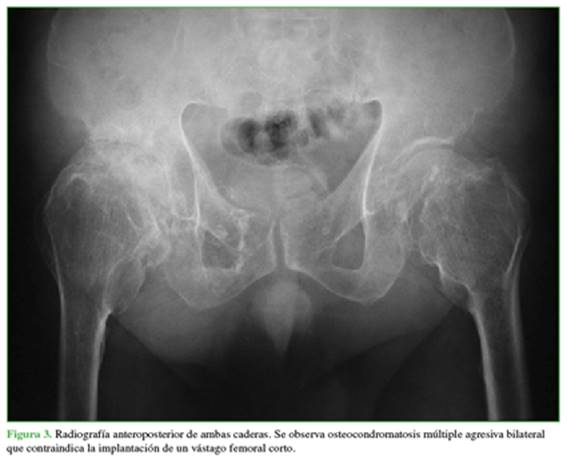

Las contraindicaciones para el uso de vástagos cortos en cirugía primaria de cadera incluyen la edad >60 años, una deformidad traslacional metafisaria severa del fémur, osteoporosis severa o patologías en las que exista una importante discordancia entre el tamaño del cuello y la metáfisis femoral, por ejemplo, en una osteocondromatosis múltiple (Figura 3).